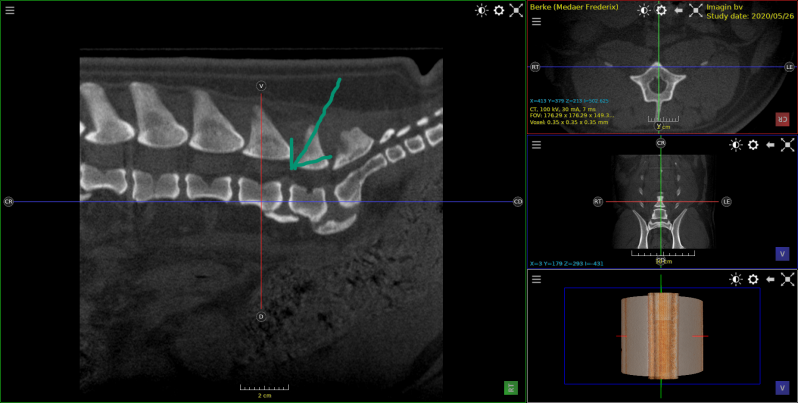

Hond Fila braziliero , van 7 maanden met tandwortel abces .

Gedeelte van het bot rond de tandwortel was aangetast .